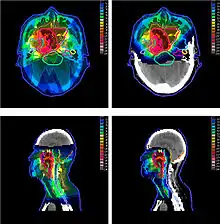

The figure at the right of the page shows how beams of X-rays (IMRT; left frame) and beams of protons (right frame), of different energies, penetrate human tissue. A tumor with a sizable thickness is covered by the IMRT spread out Bragg peak (SOBP) shown as the red lined distribution in the figure. The SOBP is an overlap of several pristine Bragg peaks (blue lines) at staggered depths.

In most treatments, protons of different energies with Bragg peaks at different depths are applied to treat the entire tumor. These Bragg peaks are shown as thin blue lines in the figure in this section. It is important to understand that, while tissues behind (or deeper than) the tumor receive almost no radiation from proton therapy, the tissues in front of (shallower than) the tumor receive radiation dosage based on the SOBP.